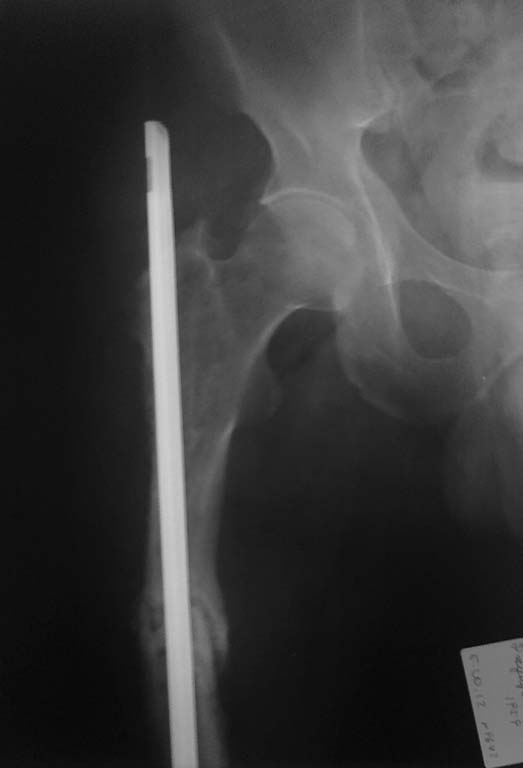

Последствие остеосинтеза бедренной кости

Только по поводу перелома бедренной кости 2-операция. 1.открытая репозиция экстрамедуллярный металлоостеосинтез. Через 6-7 мес перелом импланта. 2. удаление пластины и интрамедуллярный металлоостеосинтез гвоздем Кюнчера (2010г). В данный момент разгибательная контрактура коленного сустава, укорочение правой н/к на 4-5 см, боли в области правого тазобедренного сустава и бедра. Потологической подвижности не определяется, передвигается с помощью костылей.

На рентгенограмме признаки консолидации слабо визуализируются, дистальный конец стержня перфорировал метаэпифиз бедренной кости (в коленном суставе), проксимальный конец бедренной кости так же разрушен. Планируем варианты удаление стержня, рассверливания КМК, БИОС анатомическим бедренным стержнем + удаление металлоконструкций из других костей. У кого какое мнение и тактика в данном случае. Заранее всем спасибо. P.S: удлинение сегмента пациент не хочет (-устал от операции)